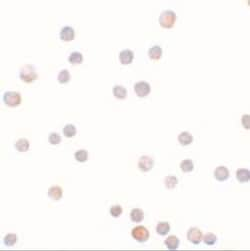

ZEB1 Polyclonal antibody specifically detects ZEB1 in Human samples. It is validated for Western Blot, ELISA, Immunohistochemistry, Immunocytochemistry/ Immunofluorescence, Immunohistochemistry (Paraffin)

| Western Blot, ELISA, Immunohistochemistry, Immunocytochemistry, Immunohistochemistry (Paraffin) | |

| Western Blot 1 μg/mL, ELISA 1:100-1:2000, Immunohistochemistry 5 μg/mL, Immunocytochemistry/ Immunofluorescence 20 μg/mL, Immunohistochemistry-Paraffin 5 μg/mL | |